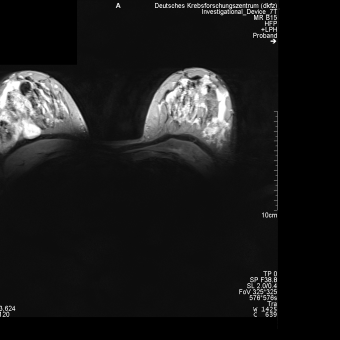

DKFZ Heidelberg, Germany: In vivo images of a healthy volunteer obtained with the 4 channel breast array using a fl3d1_ns sequence (left) and a tse2d1 sequence (right).